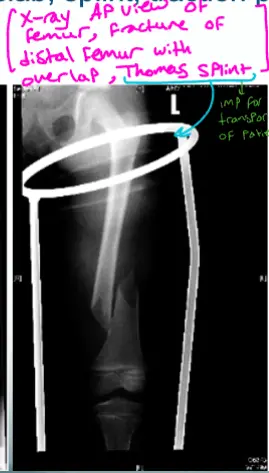

- X-ray AP view of Lt femur, fracture of distal femur with slab, Thomas splint

- Site: midâshaft left femur

- Type: simple

- Fracture line: short oblique

- Displacements: medial shift with overlap

- Special issues: hematoma

- Knee joint: not seen

- View: no lateral view